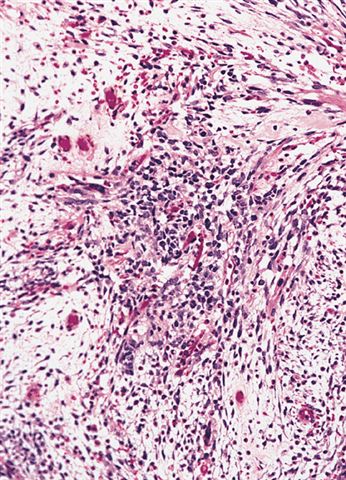

- Composed of primitive mesenchymal cells that show variable degrees of skeletal muscle differentiation

- They are moderately cellular but in the typical pattern often contain both hypocellularity and hypercellular areas with a loose, myxoid stroma

- Perivascular condensations of tumor cells in the less cellular regions are common

- Sheets of small, stellate, spindled or round cells with scant or deeply eosinophilic cytoplasm and eccentric, small oval nuclei with a light chromatin pattern and inconspicuous nucleoli

- Can occasionally identify tumor cells that contain generous amounts of eosinophilic cytoplasm, a feature of rhabdomyoblastic differentiation (so called strap cells)

- May have cells with elongated tails of cytoplasm (tadpole cells)

Microscopic (histologic) images

Contributed by Erdener Özer, M.D., Ph.D. and Mark R. Wick, M.D.

Contributed by Carolina Martinez Ciarpaglini, M.D., Ph.D. (Case #276) - tonsillar mass